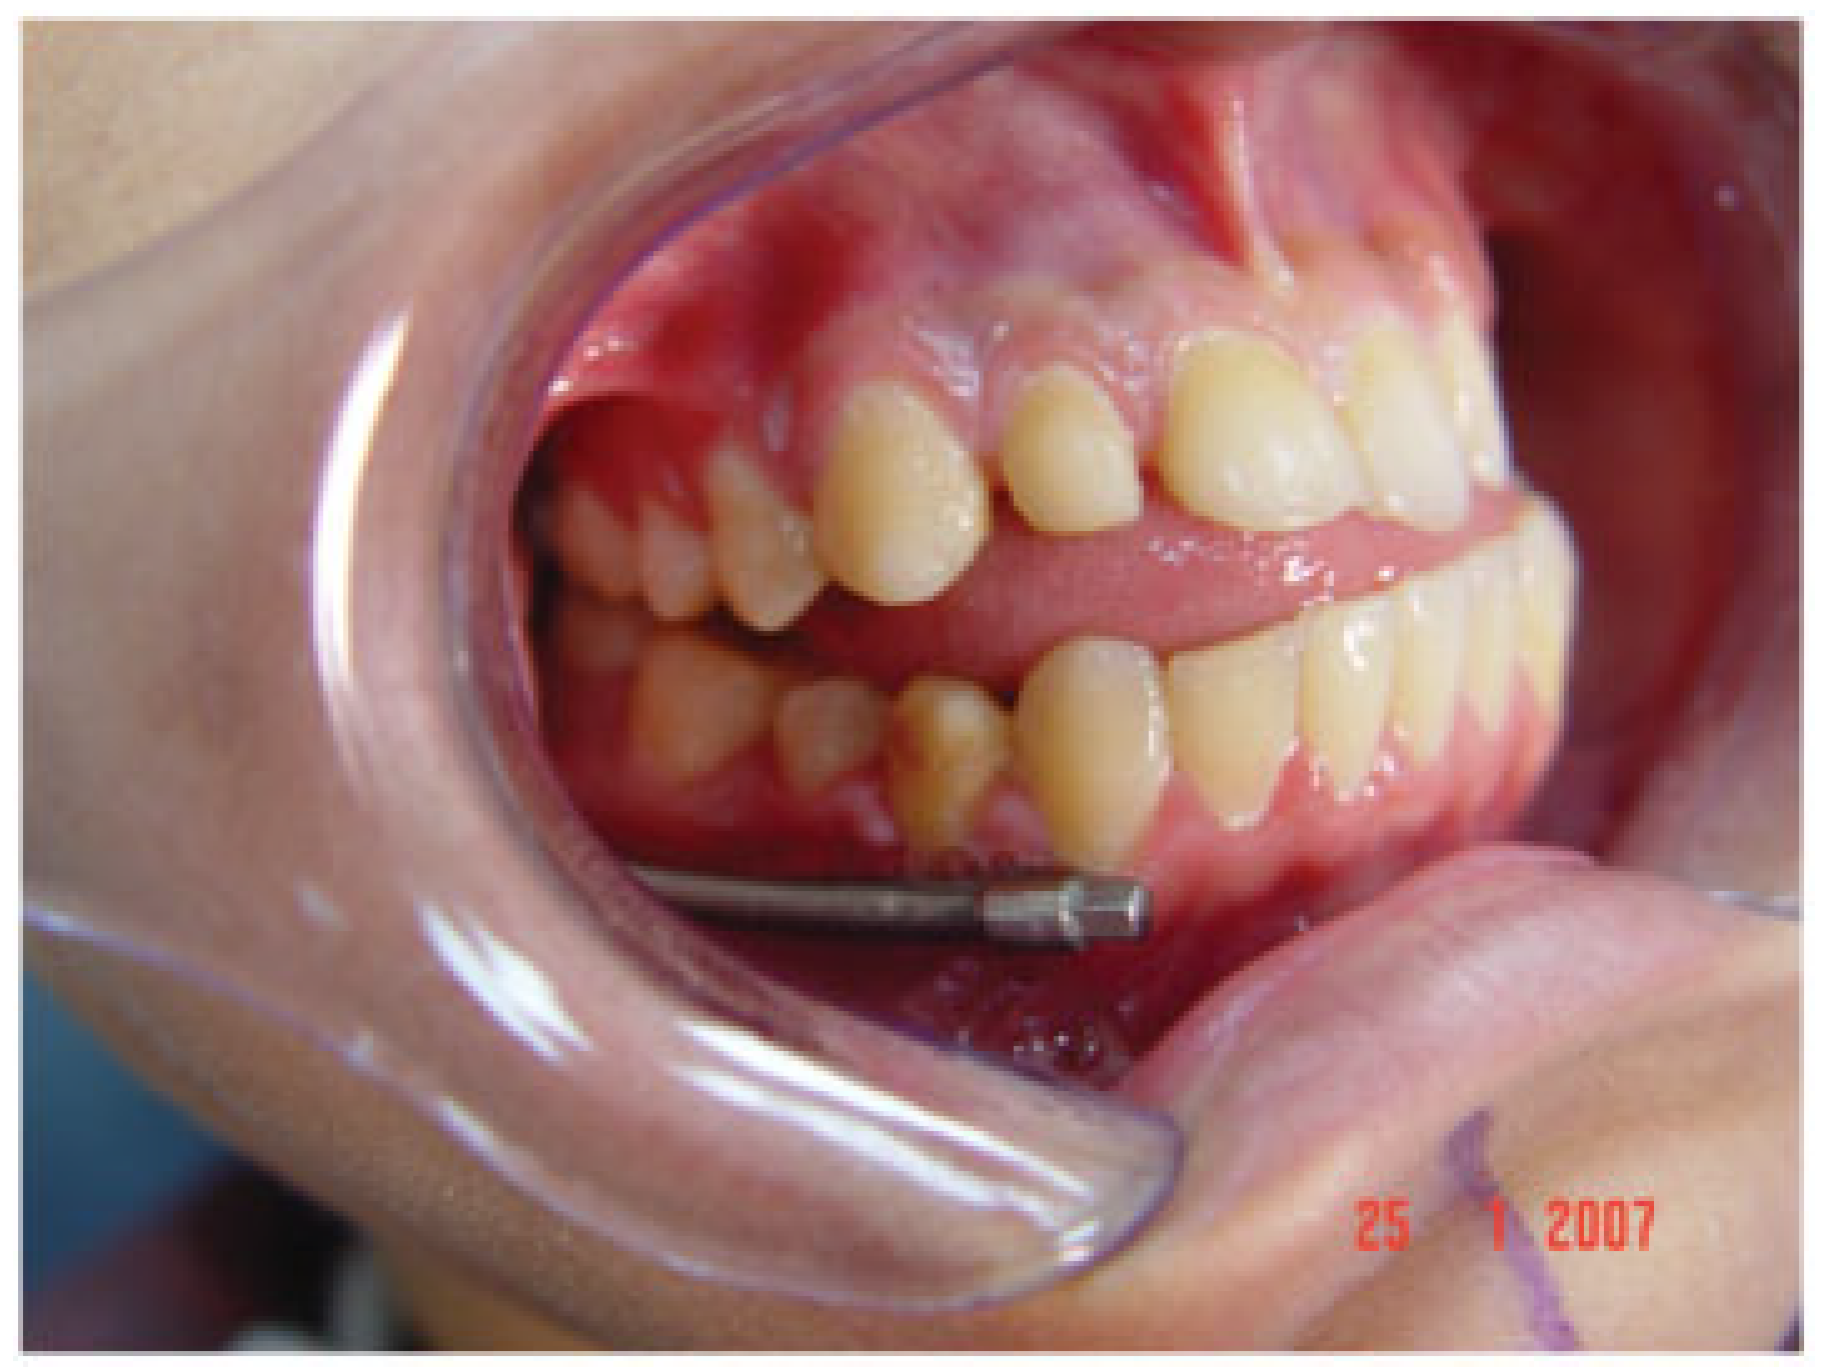

Figure 1. The patient on presentation with severe limitation in opening.

A young boy presented to the Maxillofacial Surgery Service with a severe limitation in mouth opening (Figure 1). He had problems with eating and difficulty in maintaining oral hygiene. He displayed facial asymmetry with a shift of both his facial and dental midlines to the right. There was also an alteration of the occlusal cant of the maxilla with the left side being lower than the right. He had fallen as a child some years previously and fractured the right mandibular condyle. An orthopantomogram radiograph (OPG; Figure 2) showed marked changes in TMJ anatomy and architecture on the affected right side and a hypertrophied right coronoid process.

Clinical evaluation consisted of watching for improvements in both the dental and facial midlines and whether the mandibular deviation associated with mouth opening improved. On completion of distraction, a post mandibular distraction osteogenesis OPG was taken (Figure 13A). In anticipation of continued growth from the unaffected side and possible relapse, mandibular distraction was continued beyond the dental midline (Figure 13B).